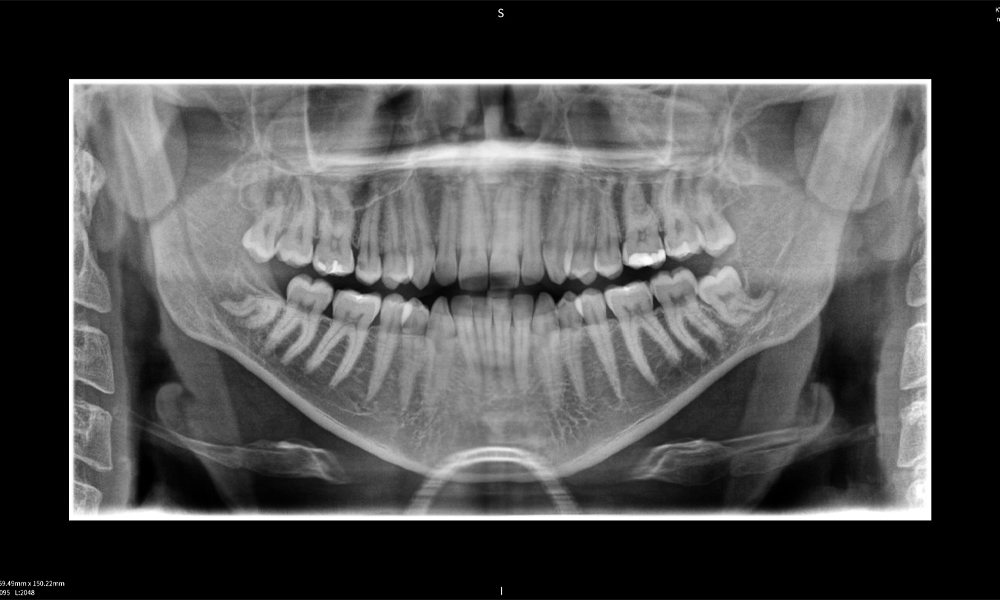

Below you will find a case from Dr. med. dent. Oliver A. Centrella, in which the CBCT images obtained with Seethrough Max provided crucial information on the complex anatomy and the critical relationship between the wisdom teeth and the inferior alveolar nerve. In this case, there is a indication for the surgical removal of the wisdom teeth.

Figure a: Imaging results of Seethrough Max, in front of a black background.

Figure a

Figure e: The panoramic X-ray serves as an initial assessment tool, showing the general positioning of the teeth as well as any potential pathological changes. Notably, on the right side (tooth 48), the situation following a crown amputation performed by an external practitioner is visible. The two severely curved roots remain in close topographical proximity to the inferior alveolar nerve within the bone. This suggests a deliberate decision to avoid the increased risk of nerve injury during a complete extraction, and represents a clinically relevant finding. In summary, CBCT scans with Seethrough Max, provide crucial information about the complex anatomy and the critical relationship between the wisdom teeth and the inferior alveolar nerve. This detailed preoperative diagnostic imaging is essential for safe and successful surgical procedures in the mandibular region.